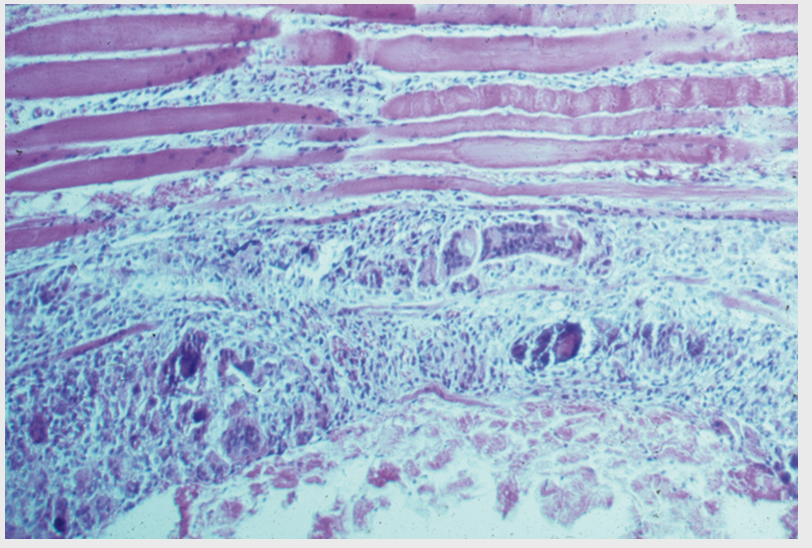

Dystrophinnopathy

Muscle biopsy showing extensive muscle cell necrosis with macrophages, mineralization, and rows of activated satellite cells indicative of regeneration in a young male golden retriever with dystrophinopathy. Hematoxylin and eosin stain.

What would be your firs DD?

Young retriever dog with slowly progressive PNS signs and elevated muscle enzyme activity.